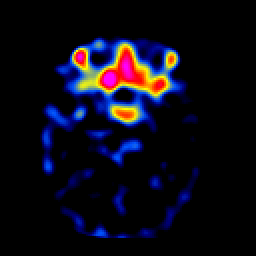

SPECT TL Study #2 -- Slice #18

[Home][Help][Clinical][Tour 1][Tour 2][Tour 3] Slice 18